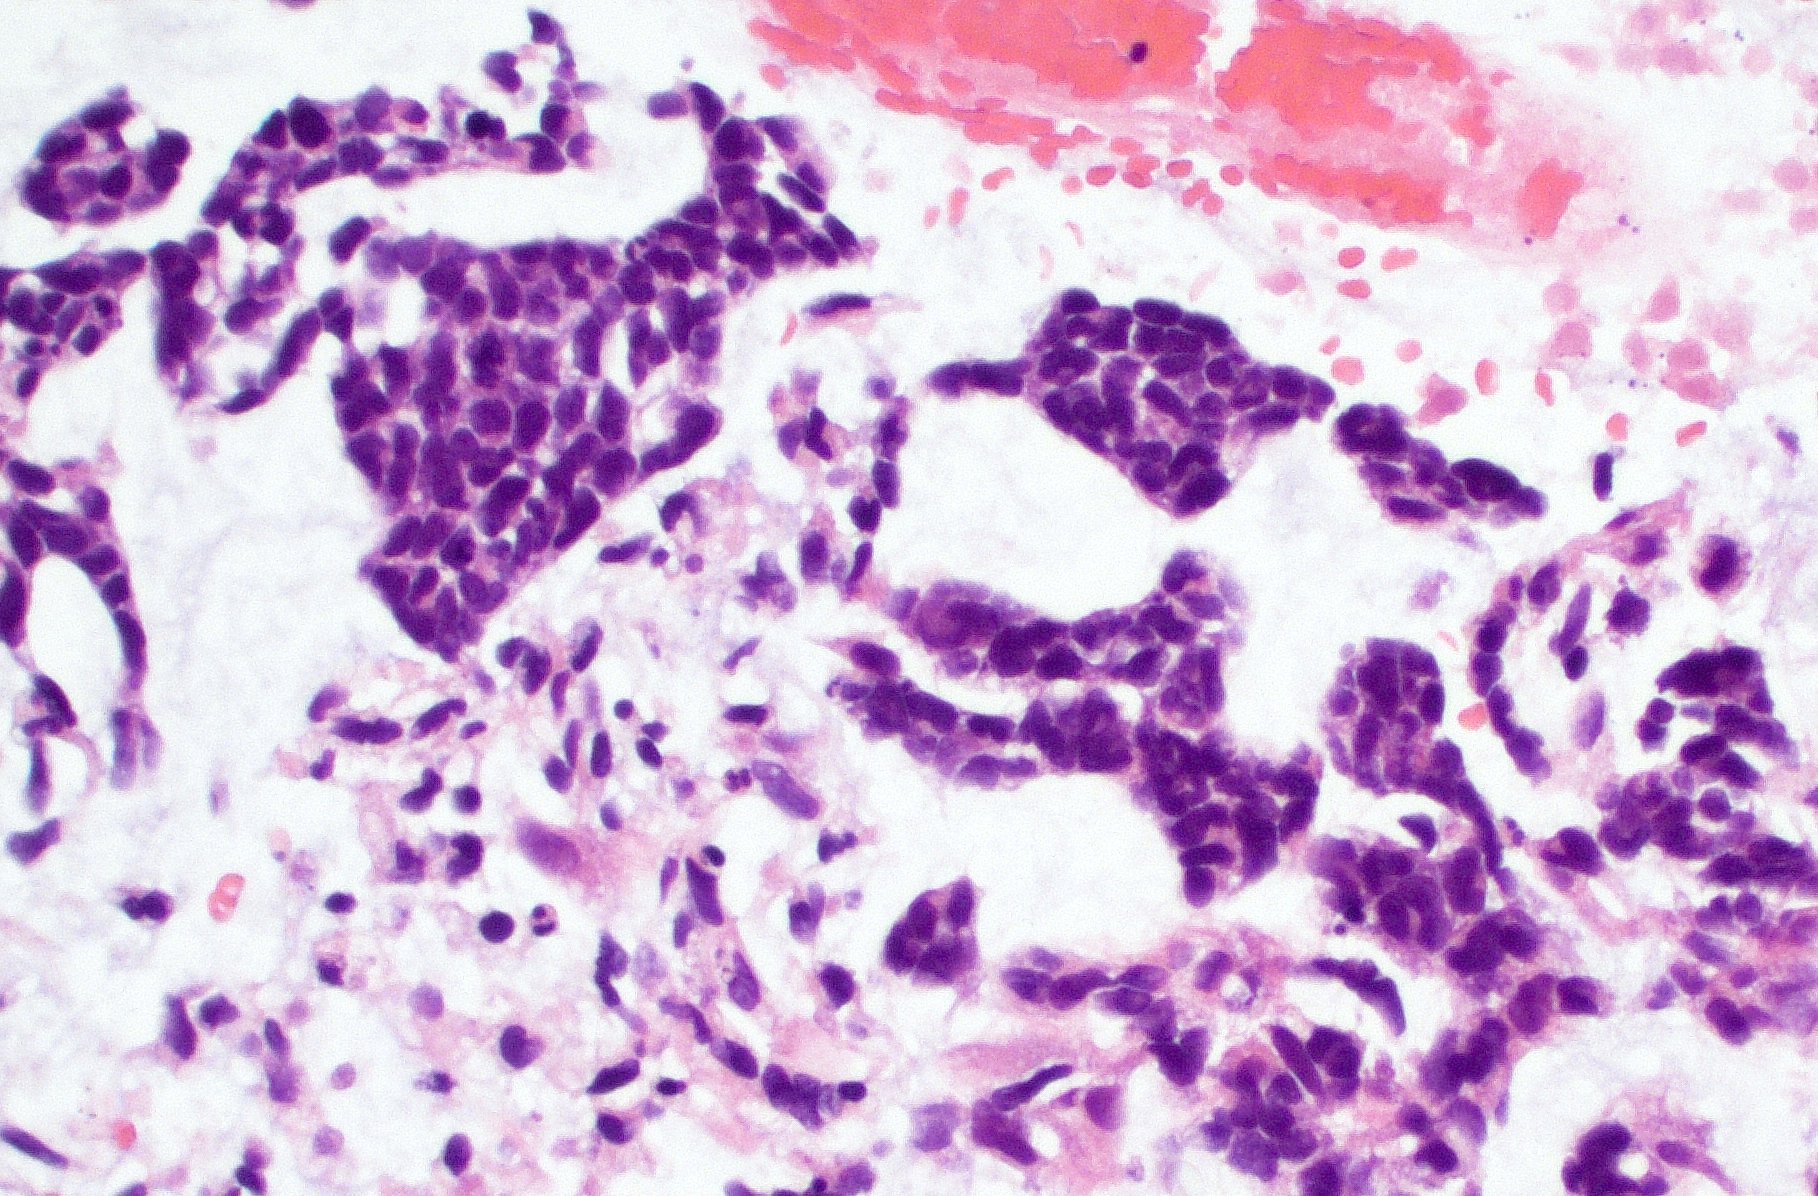

Microscopic (histologic) description

- Infiltrating, hypercellular astrocytic neoplasm often with hyperchromatic, elongated nuclei and irregular nuclear membranes

- Microvascular proliferation or necrosis is required for a histologic diagnosis of GBM

- Microvascular proliferation: multilayered, small caliber vessels with glomeruloid appearance (J Neuropathol Exp Neurol 1992;51:488)

- Necrosis: can be geographic or pseudopalisading with neoplastic cells surrounding central necrosis

Microscopic (histologic) images

Contributed by Bharat Ramlal, M.D. and Meaghan Morris, M.D., Ph.D.